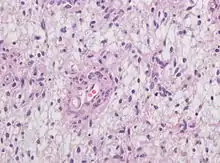

Neuropathology

Neuropathology is a specialty within the study of pathology focused on the disease of the brain, spinal cord, and neural tissue.[21] This includes the central nervous system and the peripheral nervous system. Tissue analysis comes from either surgical biopsies or post mortem autopsies. Common tissue samples include muscle fibers and nervous tissue.[22] Common applications of neuropathology include studying samples of tissue in patients who have Parkinson's disease, Alzheimer's disease, dementia, Huntington's disease, amyotrophic lateral sclerosis, mitochondria disease, and any disorder that has neural deterioration in the brain or spinal cord.[23][24]